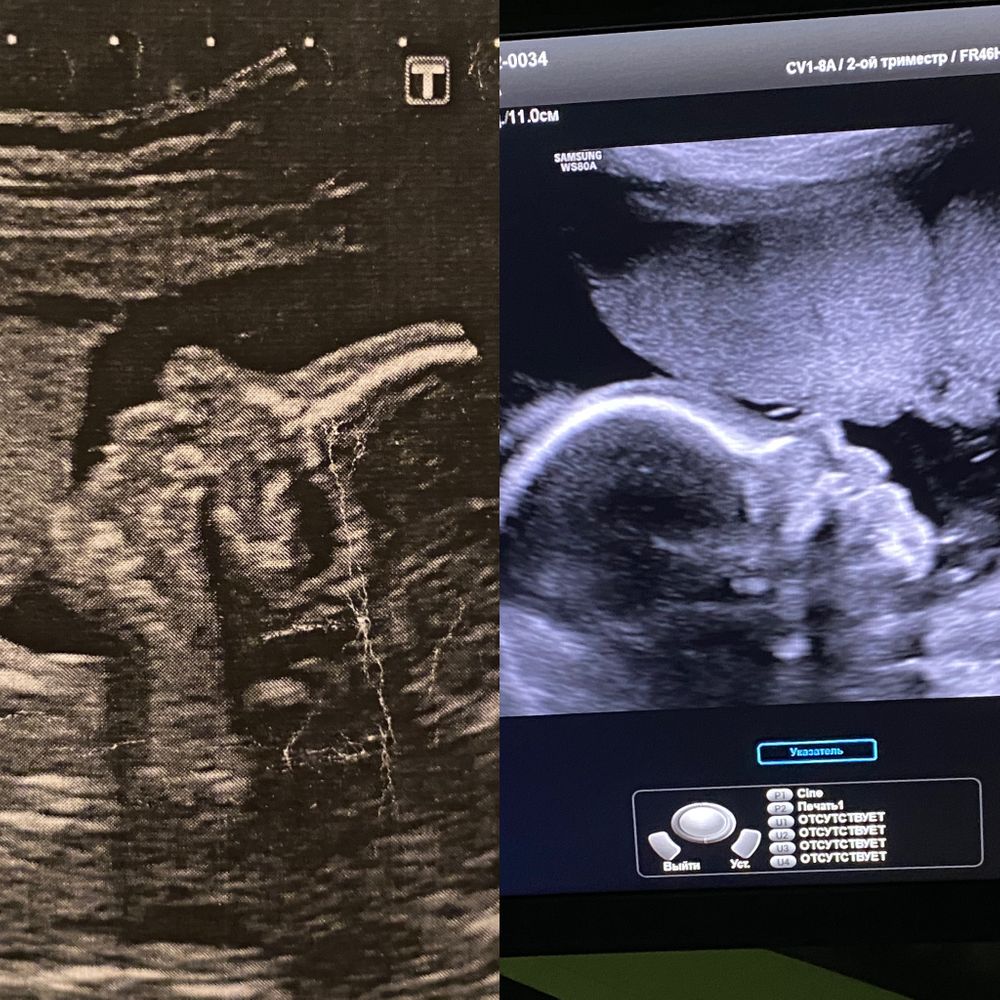

24 недели 🥲💓💓💓

Через неделю узи контрольное ,как раз в 3д распечатаю фото )

А так на узи были увеличены боковые желудочки ,но перерыв все ,я сделала вывод что это не критично 🙌🏻

Ещё профиль у неё прям совсем другой ,губы пухлые ,сразу видно что мои 😅Носик такой кнопочный ,после того как увидела ее в 3Д ,мне прям интересно знать как она будет выглядеть )

Но с младшей они уже даже профилем не схожи )

А вот и узи младшей и свеженькой )Ну разные же крошки )